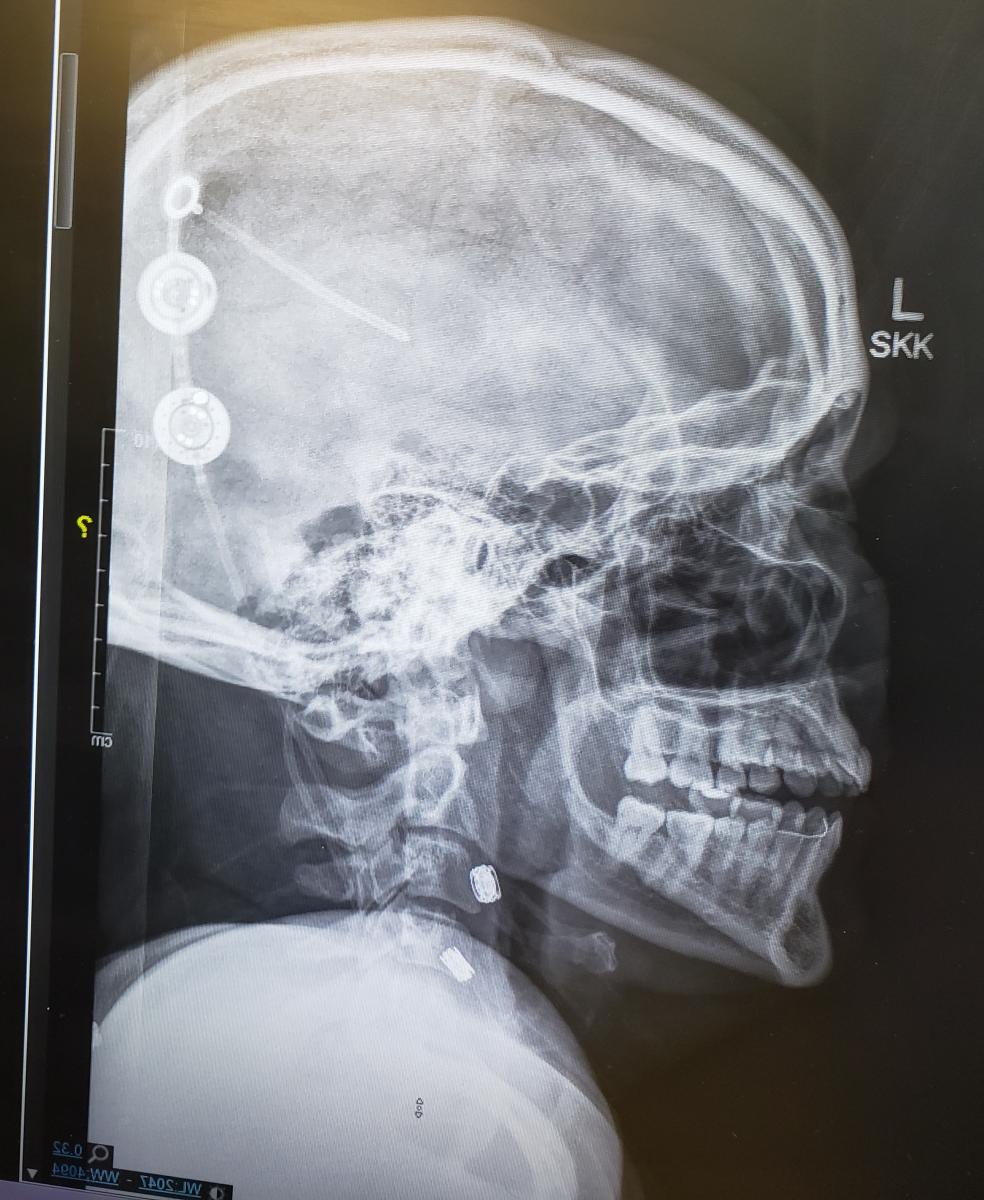

Thrown into the mix of what can be 18-hour days, she battled a new round of medical problems of her own: a COVID diagnosis and a shunt malfunction that caused worsening headaches and nausea with a jolt of pain every time she moved or stood up. She required two additional neurosurgeries to monitor the pressure inside her brain, and then to replace the shunt or tubing system that begins in her brain and ends in her lower body to drain excess cerebrospinal fluid.

The treatment is a shunt, a permanent surgically implanted internal drainage system that has the purpose of draining enough, but not too much, spinal fluid. It’s possible to drain too much spinal fluid or to not drain enough.

The flow through modern shunts is regulated by a spring valve mechanism that can be adjusted to make it easier or harder for spinal fluid to flow through, similar to adjusting the tension on a screen door.

That means the shunt can be adjusted to make it easier to open or harder to open. The tendency for shunts to drain too much when the patient is upright can cause headaches. Some shunts have a second valve mechanism to counteract the effect of gravity when a person is upright.